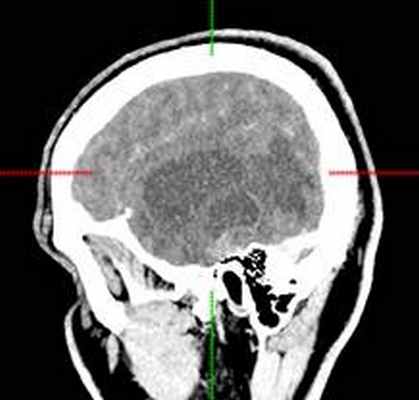

КТ головного мозга с контрастным усилением (24.03.2015): объемное кистозно-солидное образование правой теменно-височно-лобной области. Дислокационный синдром.

22.10.2015 была выполнена операция: микрохирургическое удаление опухоли правой височной доли под интраоперационными навигационным контролем и с интраоперационной фотодинамической терапией.

КТ головного мозга (23.10.2015): не выявило признаков кровоизлияния или каких-либо других хирургических осложнений в области оперативного вмешательства.